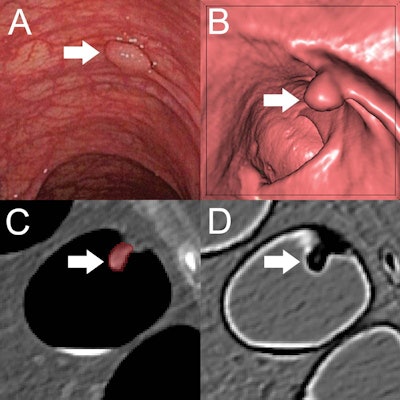

The researchers sought to make up for this shortcoming with machine learning-based analysis of CTC radiomics. They developed their random-forest classification model using a training set of 107 colorectal polyps from 63 patients that included 169 manual segmentations on the CTC images. Polyps were classified as either benign (hyperplastic polyp or regular mucosa) or premalignant (adenoma) based on histopathology.

The researchers assessed the model's classification performance and generalizability on datasets from a North American multicenter CTC screening trial available from the Cancer Imaging Archive. This set of cases comprised 77 polyps in 59 asymptomatic patients with an average risk of colorectal cancer and included CTC exams acquired on CT scanners from several different vendors and with varying protocols.